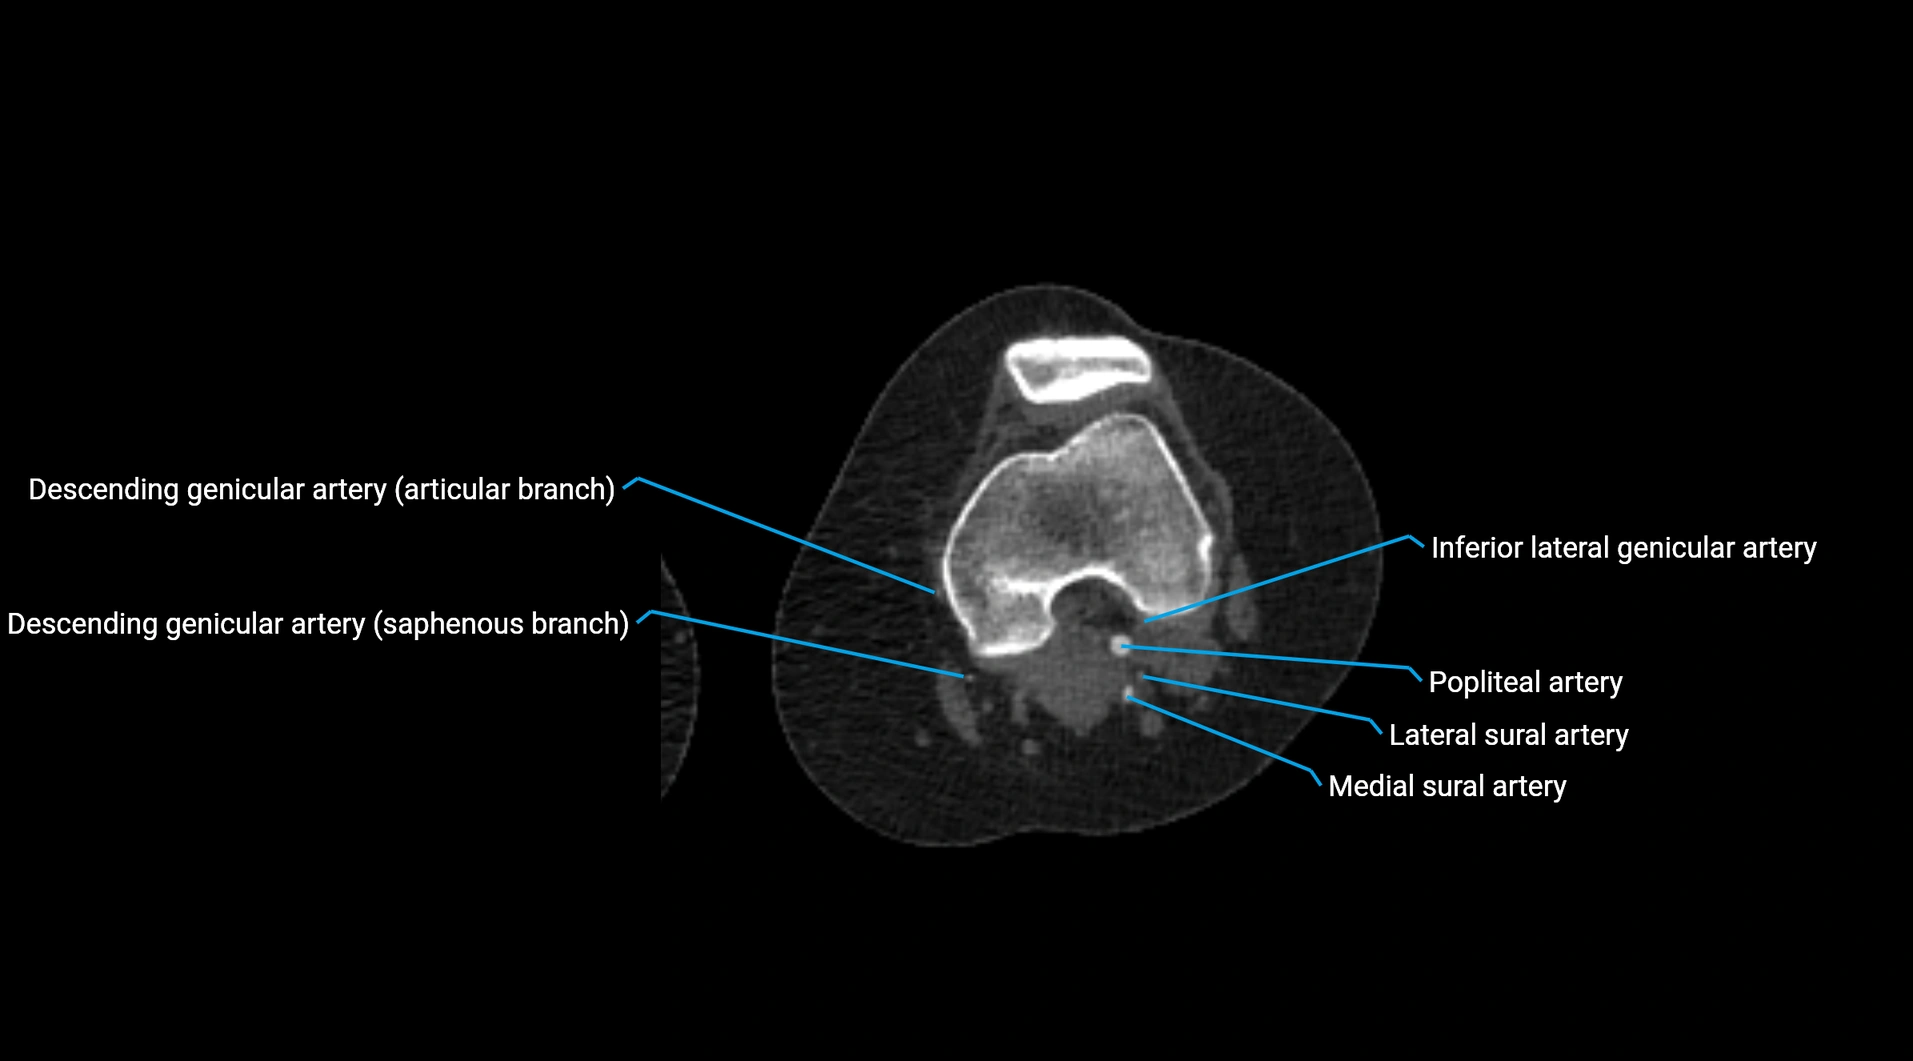

Contrast-enhanced CT (CTA):

• Gold standard for abdominal aortic imaging

• Provides excellent detail of lumen, wall, aneurysm, thrombus, and branch vessels

• Multiplanar and 3D reconstructions help in aneurysm measurement, stent graft planning, and dissection evaluation

• Detects acute rupture, traumatic injury, or occlusion with high sensitivity